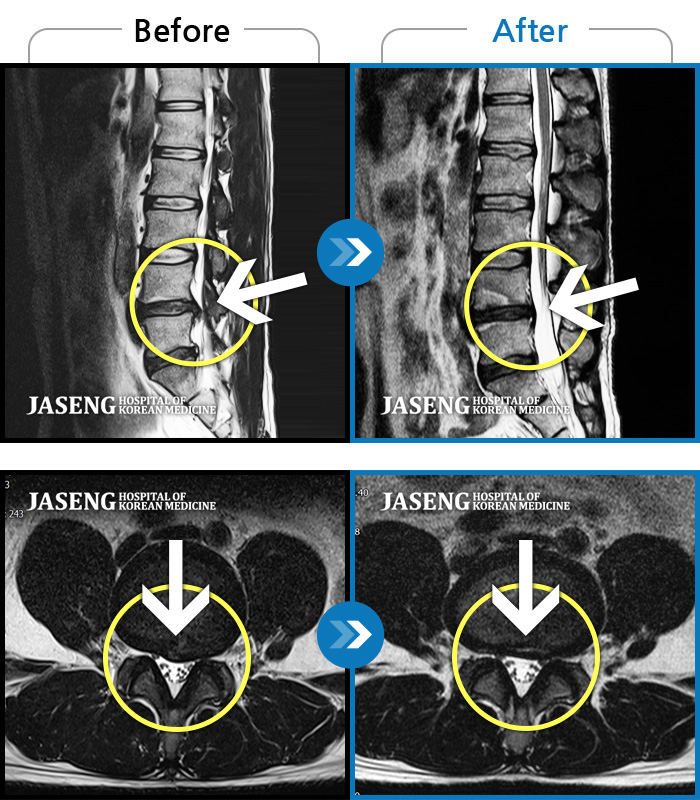

허리디스크

인천 · 조남훈 원장

허리가 너무 아프고 다리가 저려요.

촬영시기

2018.04.23 ~ 2025.12.05

2025.12.19